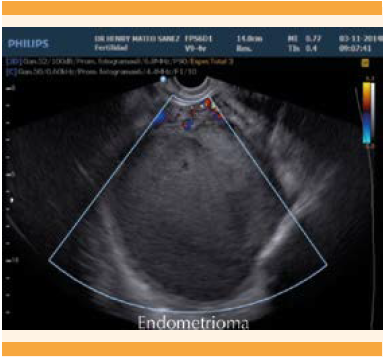

En la exploración física no se encontraron signos de fiebre ni datos de irritación peritoneal, pero percibió dolor moderado a la palpación en la fosa iliaca izquierda, que se irradiaba a la región lumbar y se extendía hasta el muslo posterior ipsilateral. En la evaluación física inicial se encontró útero en anteroversoflexión, cérvix central y posterior; a la palpación: fondo de saco posterior doloroso y ocupado por abultamiento de consistencia suave en más de 50% de la pelvis izquierda. El ultrasonido transvaginal del ovario izquierdo mostró una imagen compatible con endometrioma de 9.2 x 8.4 cm (Figuras 1 y 2).

Figura 1 Ultrasonido transvaginal (región adyacente al útero) que identifica el endometrioma de 10.8 x 10.5 cm, a expensas del ovario derecho.

Figura 2 Ultrasonido Doppler transvaginal que muestra la lesión no vascularizada.